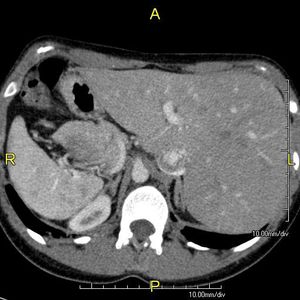

이 상태는 흉강과 복강 내의 모든 주요 장기에 영향을 미친다. 일반적으로 장기는 시상면을 기준으로 좌우가 바뀐다. 심장은 흉강의 오른쪽에, 위와 비장은 복부의 오른쪽에, 간과 담낭은 왼쪽에 위치한다. 심장의 정상적인 오른 심방은 왼쪽에, 왼 심방은 오른쪽에 위치한다. 폐의 구조도 바뀌어 왼쪽 폐는 세 개의 엽, 오른쪽 폐는 두 개의 엽을 가진다. 혈관, 신경, 림프관을 포함한 다른 내부 구조도 마찬가지로 좌우가 바뀐다.

심장이 흉강의 오른쪽에 있는 경우를 "우심증을 동반한 내장 역위증" 또는 "완전 내장 역위증"이라고 한다. 심장이 흉강의 왼쪽에 남아있는 매우 드문 경우(200만 명 중 1명 꼴)는 "좌심증을 동반한 내장 역위증" 또는 "불완전 내장 역위증"이라고 한다.

''내장 역위증''의 진단은 영상 기술, 예를 들어 X-레이, 초음파, CT 스캔, 자기 공명 영상 (MRI) 등을 사용하여 내릴 수 있다.[10]